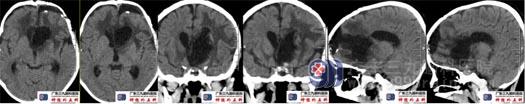

术前头颅CT鞍内示斑片状低密度影,边缘示斑点状钙化;鞍上区-左侧额叶-左侧脑室前角示一团片状高密度影,累及胼胝体,其内示多发斑片状钙化,大小约41mm×24mm×51mm,周围双侧额叶示斑片状低密度水肿影。脑室系统轻度扩大,左侧脑室受压变窄,双侧脑室后角示斑片状高密度影。头颅CTA检查:鞍内术区团块状占位性病变内血供丰富,存在多发细小血管影及钙化影,累及邻近双侧大脑前动脉A1段、A2段以上及其分支细小、狭窄,大部分显示不清;双侧大脑中后动脉存在代偿增粗延长。